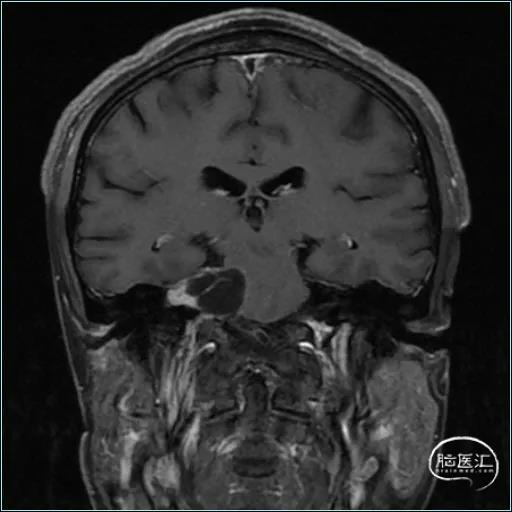

术前影像资料

扩大的内听道

患者:男, 56y,左耳听力下降半年加重3月

肿瘤最大径约3.6cm